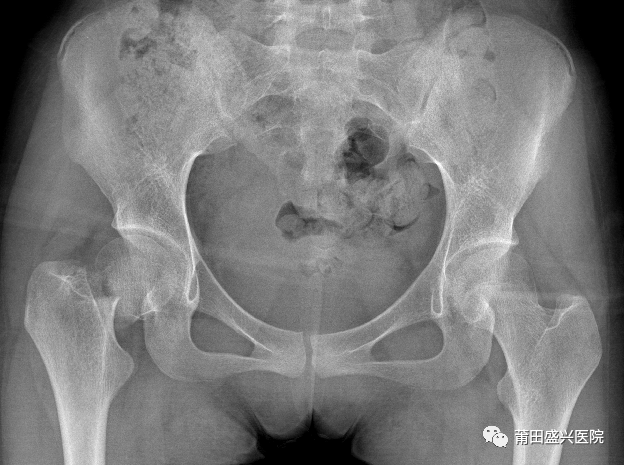

病例分享:患者林某,女,14歲,外傷致右髖疼痛活動(dòng)受限入住莆田盛興醫(yī)院骨科。經(jīng)檢查診斷為“右股骨頸骨折”。

經(jīng)盛興醫(yī)院骨科團(tuán)隊(duì)綜合評(píng)估后,決定為患者實(shí)施“右股骨頸骨折微創(chuàng)復(fù)位FNS內(nèi)固定術(shù)”治療。在林國(guó)兵院長(zhǎng)、黃益平主任醫(yī)師及骨科團(tuán)隊(duì)的共同努力下,手術(shù)于2022年1月18日在麻醉科及手術(shù)室醫(yī)護(hù)的全力配合下順利完成,術(shù)后透視復(fù)位佳,內(nèi)固定位置良好?;颊咝g(shù)后1周康復(fù)出院。